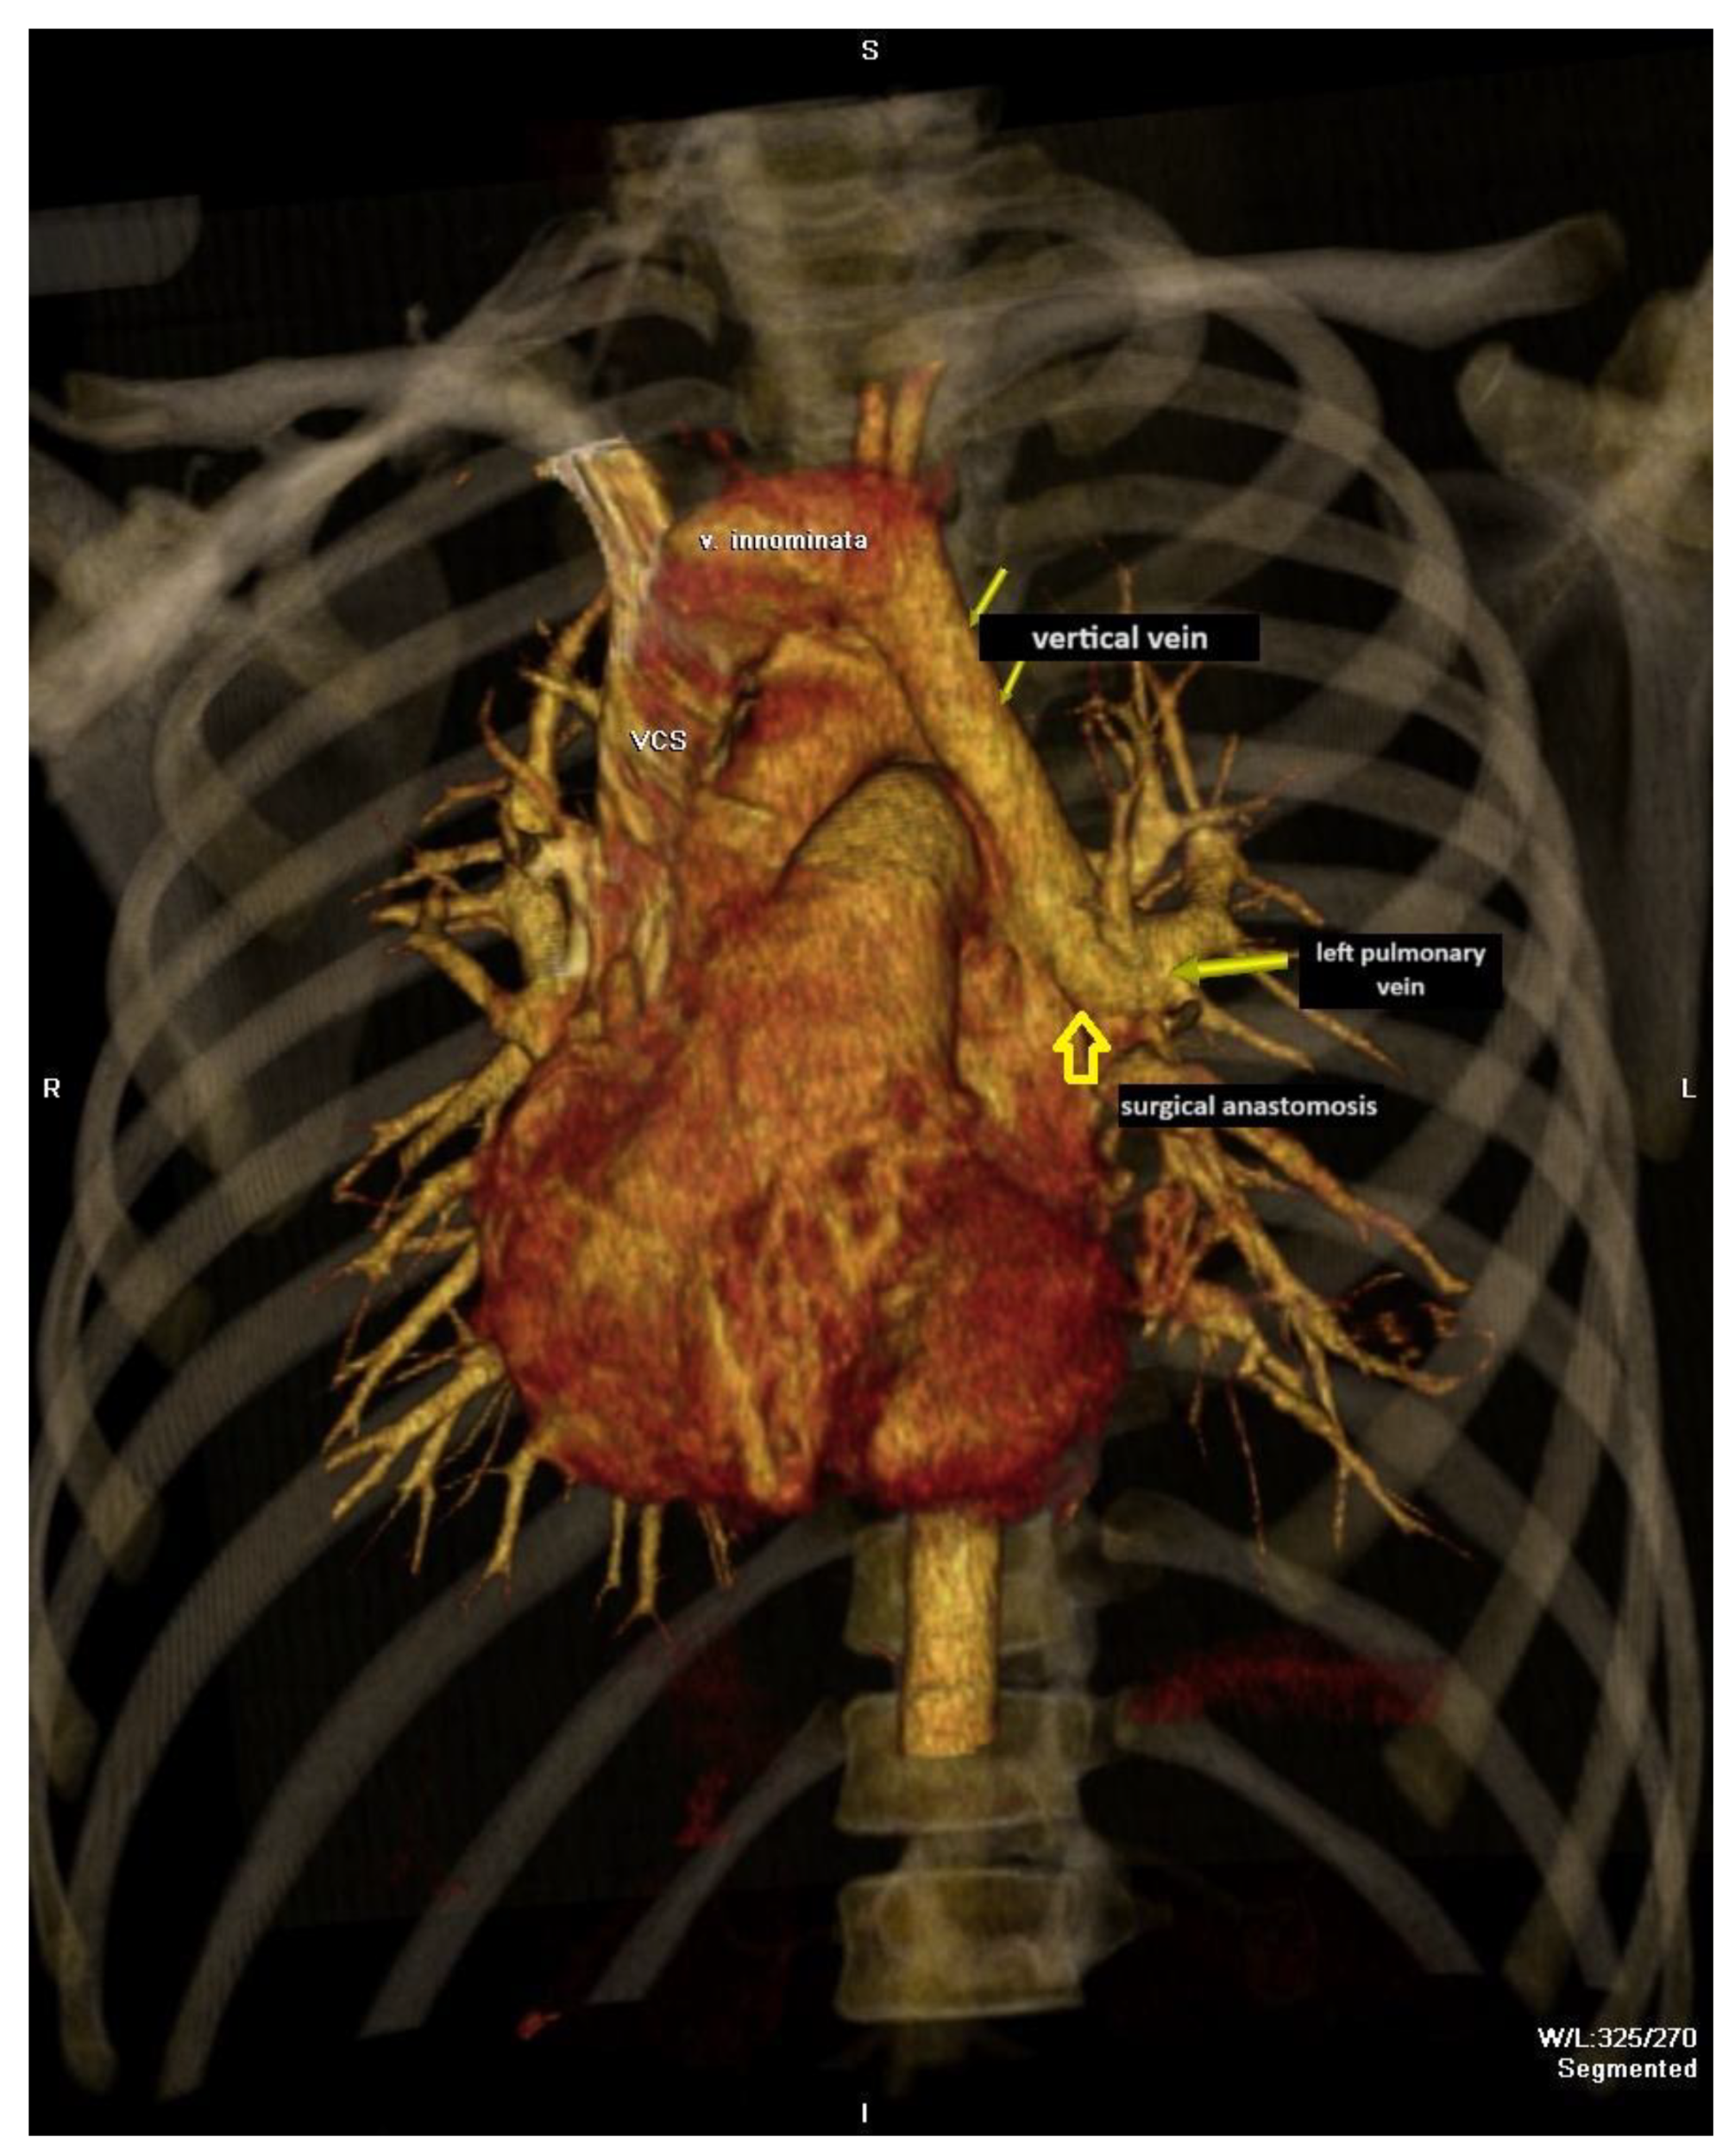

Percutaneous Embolization of No Ligated Vertical Veins After Total Anomalous Pulmonary Vein Return Operation and Risk Factors for Its Persistence